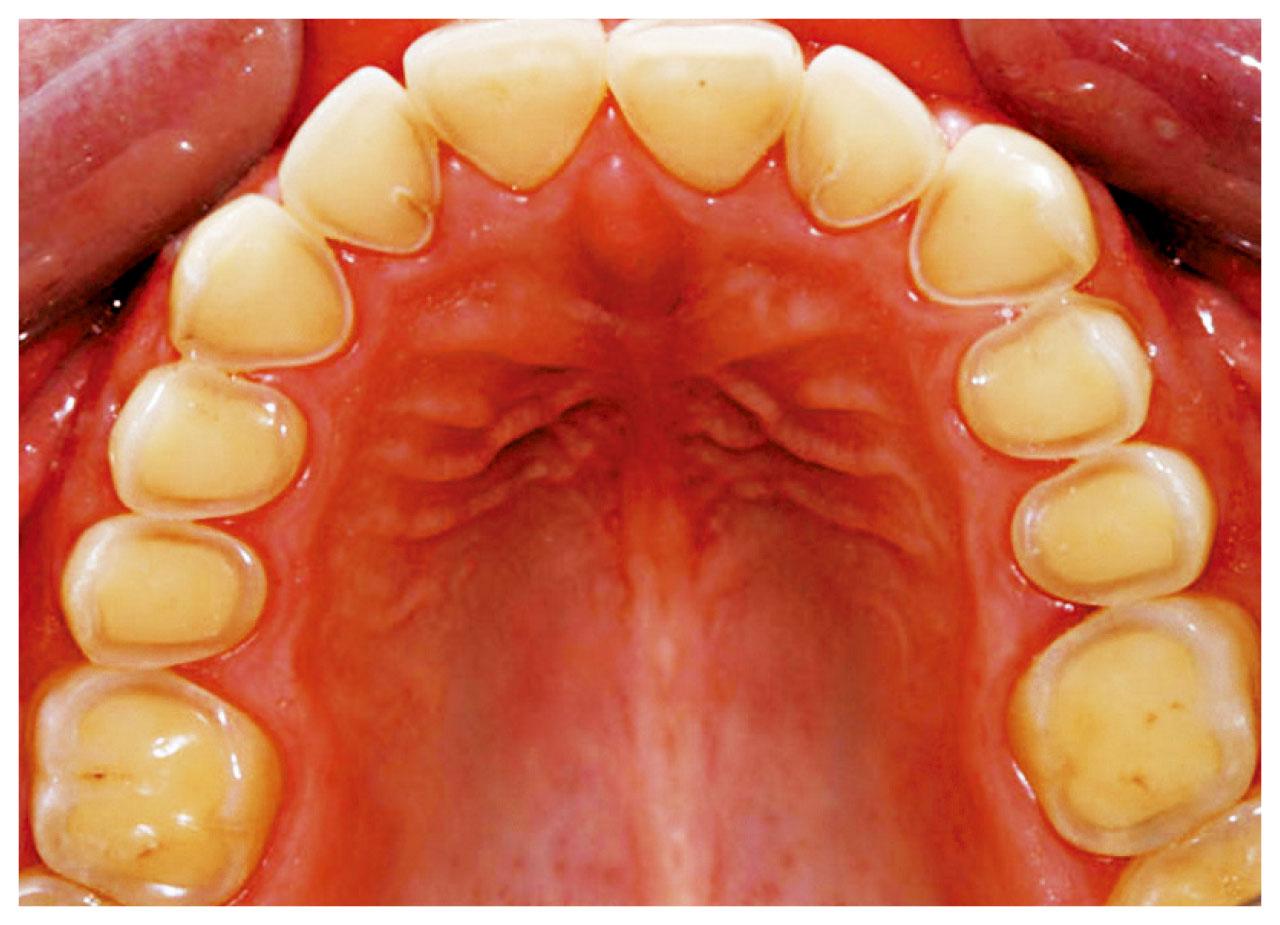

當琺瑯質變薄,便會透出偏黃色的象牙質。

初期牙齒侵蝕未必有明顯徵狀,但如情況惡化,或出現牙齒凹痕、變黃、敏感、蛀牙等,由於象牙質比琺瑯質較易被侵蝕,或使剩下的琺瑯質失去支撐,變得脆弱容易咬崩,嚴重影響日常生活。黃凌旻於臨床上遇過更嚴重情況,「除了牙齒表面的損耗外,牙房亦已收縮,並形成牙房結石,本屬人體自我保護機制,但結石或影響牙房的供血情況,可使牙神經慢慢枯死、牙齒容易受到感染。」